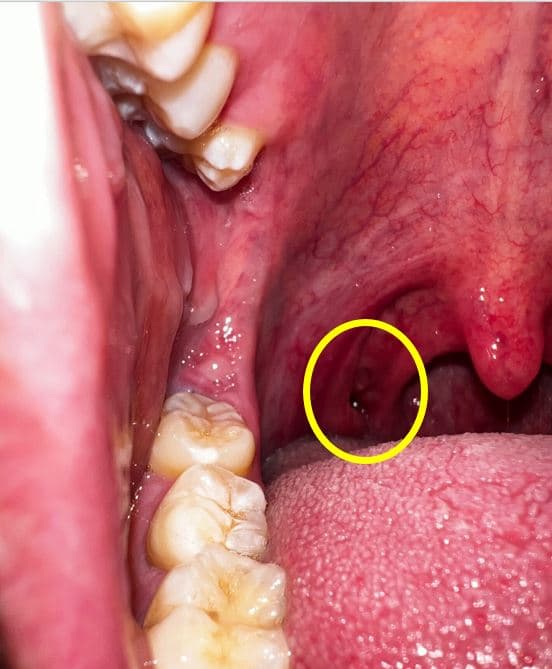

목구멍 편도 쪽에 구멍이 나있어요 이상없을까요 ?

어느순간부터 편도쪽에 이질감과 함께 편도결석의 악취가 느껴져 핸드폰으로 촬영을 해봤습니다.

확인결과 목구명 편도 쪽에(아래사진의 목구멍편도 좌측 구멍) 구멍이 있습니다.

이상없을까요 ?